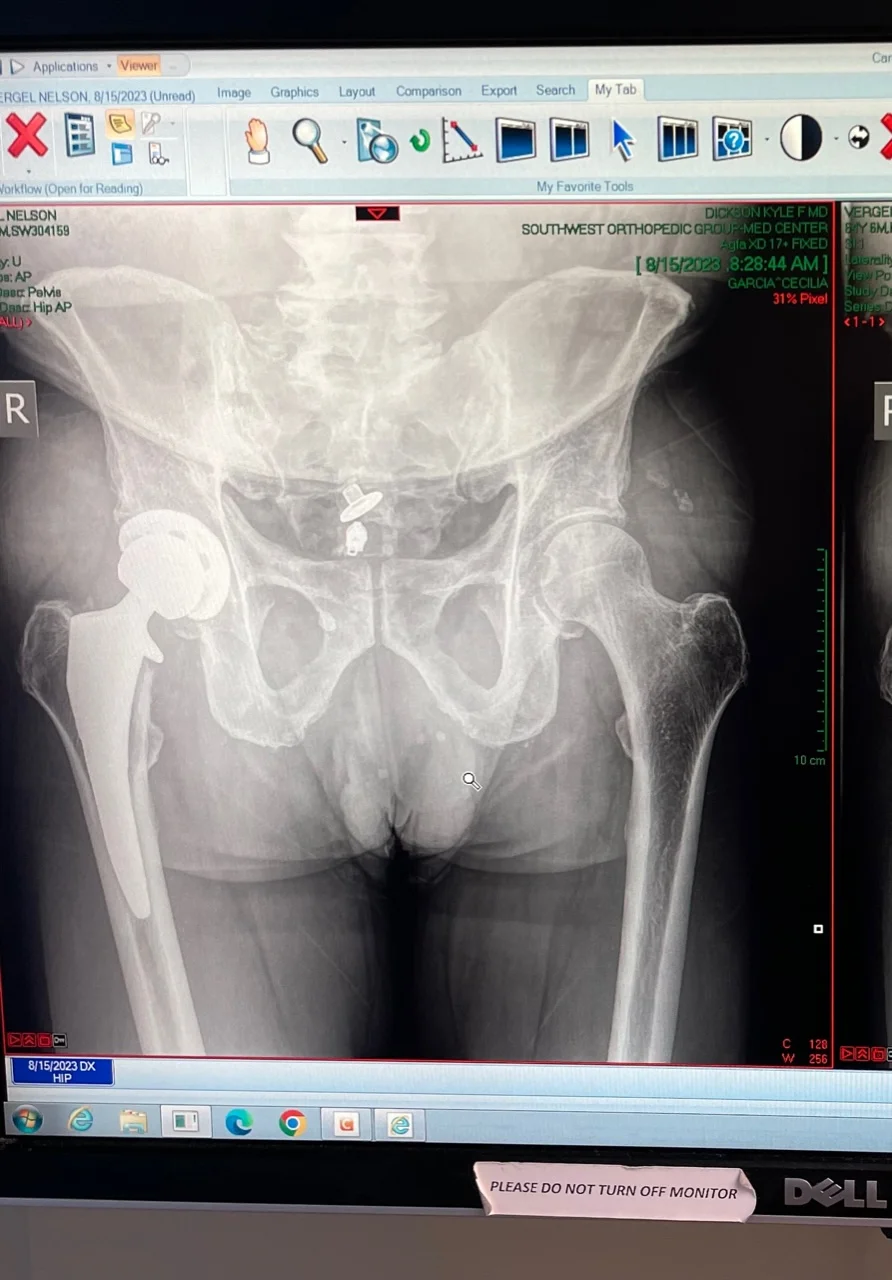

Since about March, I have experienced pain again in the hip that got replaced. It happens when I walk for over 15 minutes. My medical team is looking into it. So far, Xrays look OK. MRI and CT scan results are to be reviewed on Tuesday. I am starting to think that my pre-existing spine issues are influencing my hip flexor at the L2/L3 level. I will know more next week.